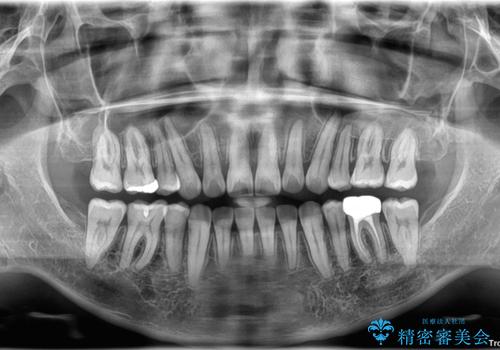

- 口元の突出感が強く、口が閉じにくいことを主訴として来院された患者さんの症例をご紹介します。

前歯部の叢生(デコボコ)も認められ、歯がきれいに並ぶためのスペースが不足している状態でした。

これらの問題を総合的に改善するため、上下左右の第一小臼歯を計4本抜歯し、スペースを確保する治療計画を立てました。

奥歯の噛み合わせがずれている「シザーズバイト」を適正に整えることで、見た目だけでなく機能性も向上し、安定した咬合が獲得できました。